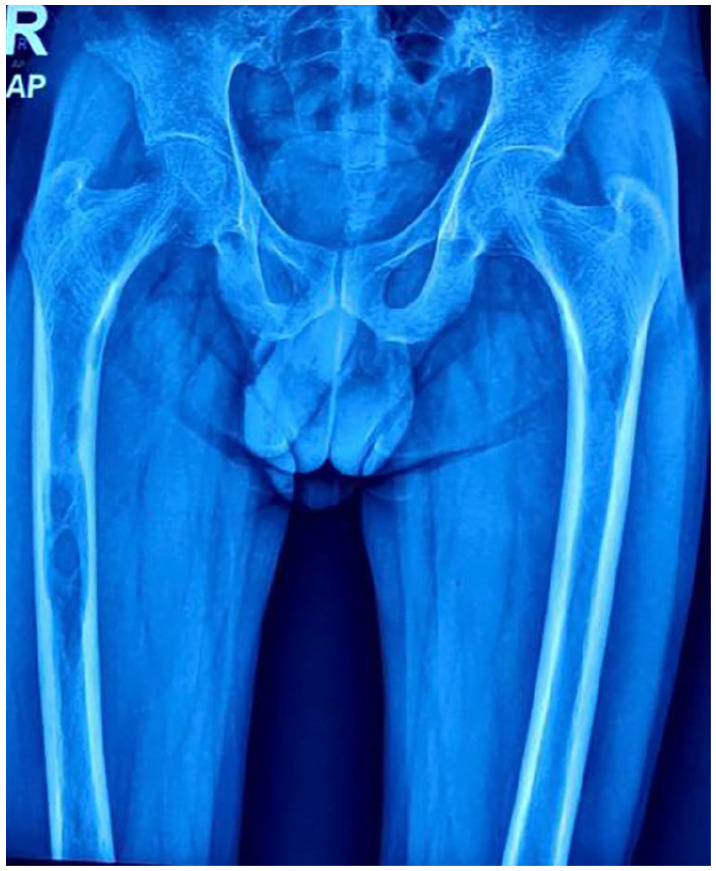

Brown tumors, though rare, are significant manifestations of hyperparathyroidism, often presenting with multifocal osteolytic lesions and occasionally leading to pathological fractures. This case report details the presentation and management of a 38-year-old male with multifocal brown tumors, including a right tibial fracture, and provides a comprehensive literature review. The patient exhibited multiple osteolytic lesions in the legs, thighs, and forearms, alongside elevated serum calcium and parathyroid hormone (PTH) levels. Management included conservative fracture treatment, surgical resection of the parathyroid adenoma, and postoperative rehabilitation. Follow-up revealed significant tibial fracture healing and reduction in the size of osteolytic lesions. This report underscores the importance of timely diagnosis and comprehensive management to prevent complications and improve outcomes in patients with multifocal brown tumors.